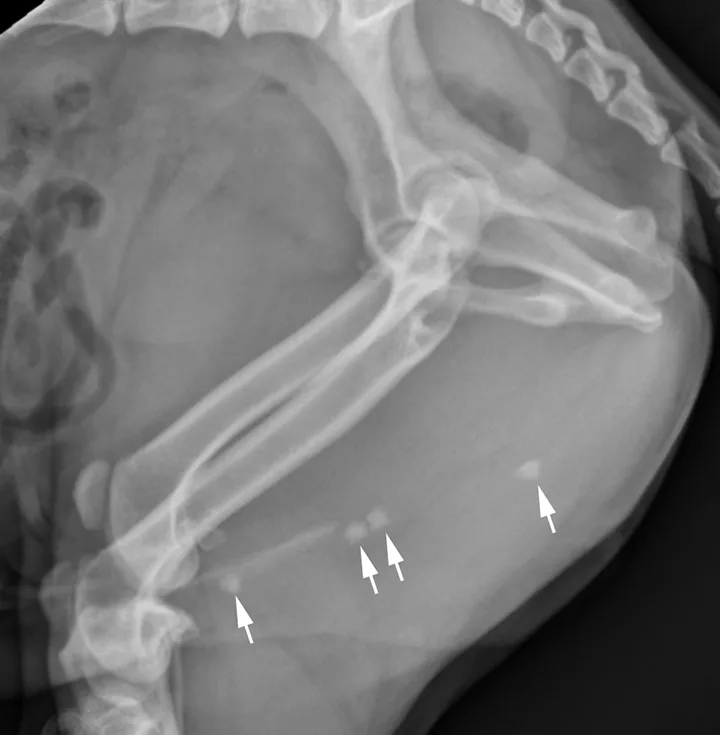

Lateral x-ray of caudal aspect of dog with arrows pointing to radiopaque objects in penile urethra.

FIGURE 10

Lateral radiograph of a male dog centered on the perineum with the pelvic limbs pulled ventrally (flexion of the pelvis at the coxofemoral joints). This radiograph documents multiple well-defined, mineral opaque calculi within the penile urethra (arrows).